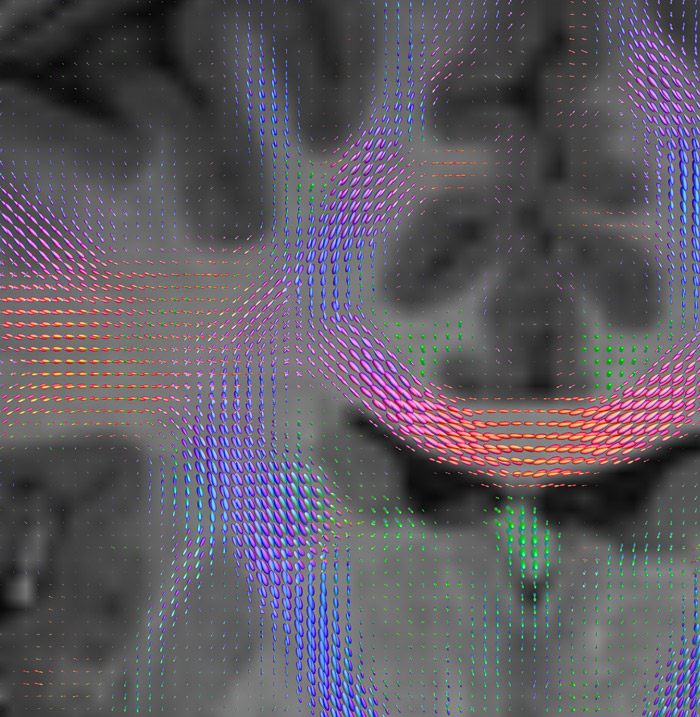

CSD of multishell DWI results in the white matter FOD at each voxel. Unlike the conventional diffusion tensor model, this approach enables accurate modeling of multiple fiber populations within a single voxel.

Crossings of the corpus callosum, corticospinal tracts, and the superior longitudinal fasciculus are shown.

Crossing fibers of the corpus callosum bordered by the superior longitudinal fasciculus as well as within in the pons.

All images were created from the same acquisition in a child using Ingenia 3.0T CX and 32-channel dS Head coil. Diffusion data was acquired at b-values 0, 500, 1000, 2000, 3000. The use of high b-values (3000 s/mm2) effectively suppresses extra-axonal water signal and provides high angular resolution.

CSD: constrained spherical deconvolution

FOD: fiber orientation density